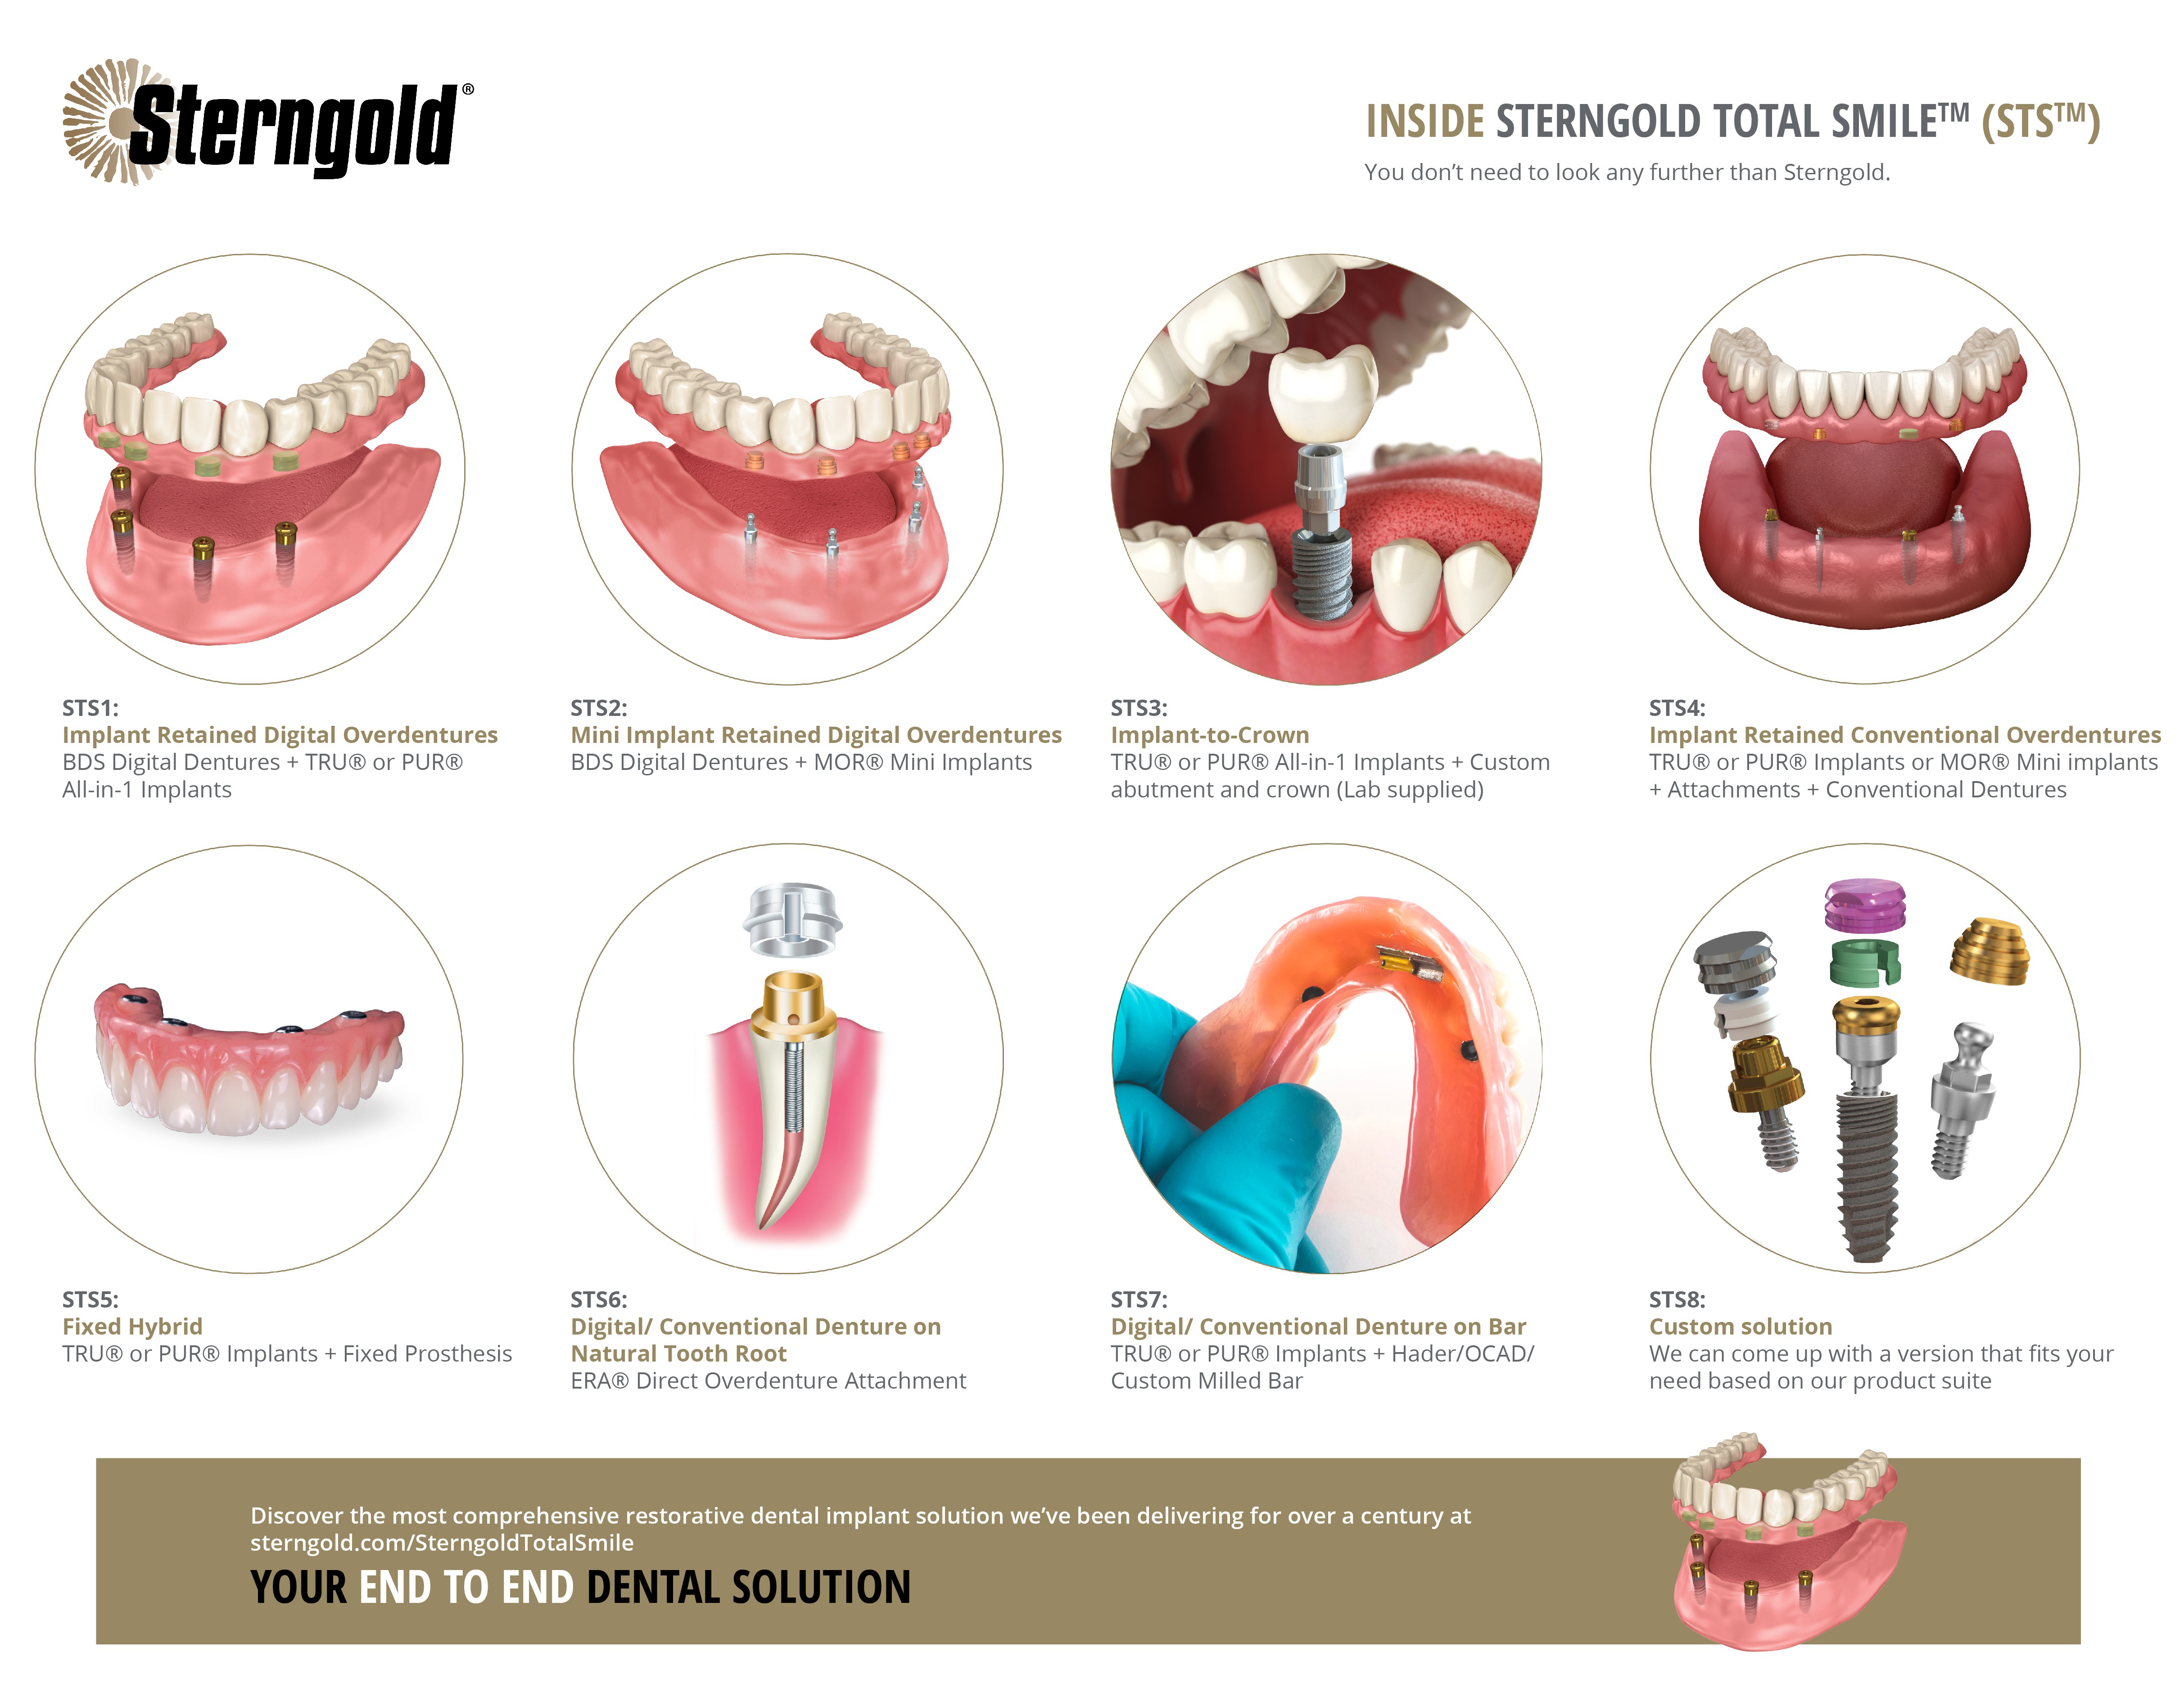

Amrulo offers a plethora of services, the most notable being the Open system designed to be compatible with any lab and software, helping dental partners to maximize their benefits. The solution is the first-of-its-kind in the industry, enabling clinical managers to trace lab results seamlessly. The recently launched tool will support and ease clinicians’ transition into the digital realm, ultimately ensuring improved clinical results and decreased procedure failures.

With the release of its new tool, Amrulo hopes to promote digital dentistry by connecting digital partners in the dental industry on a single platform that integrates all brands of scanners and 3D printers. Other features and benefits of Amrulo include time-saving affordability, increased data accuracy, enhanced office freedom, and a secure platform that connects dental care providers with experts.